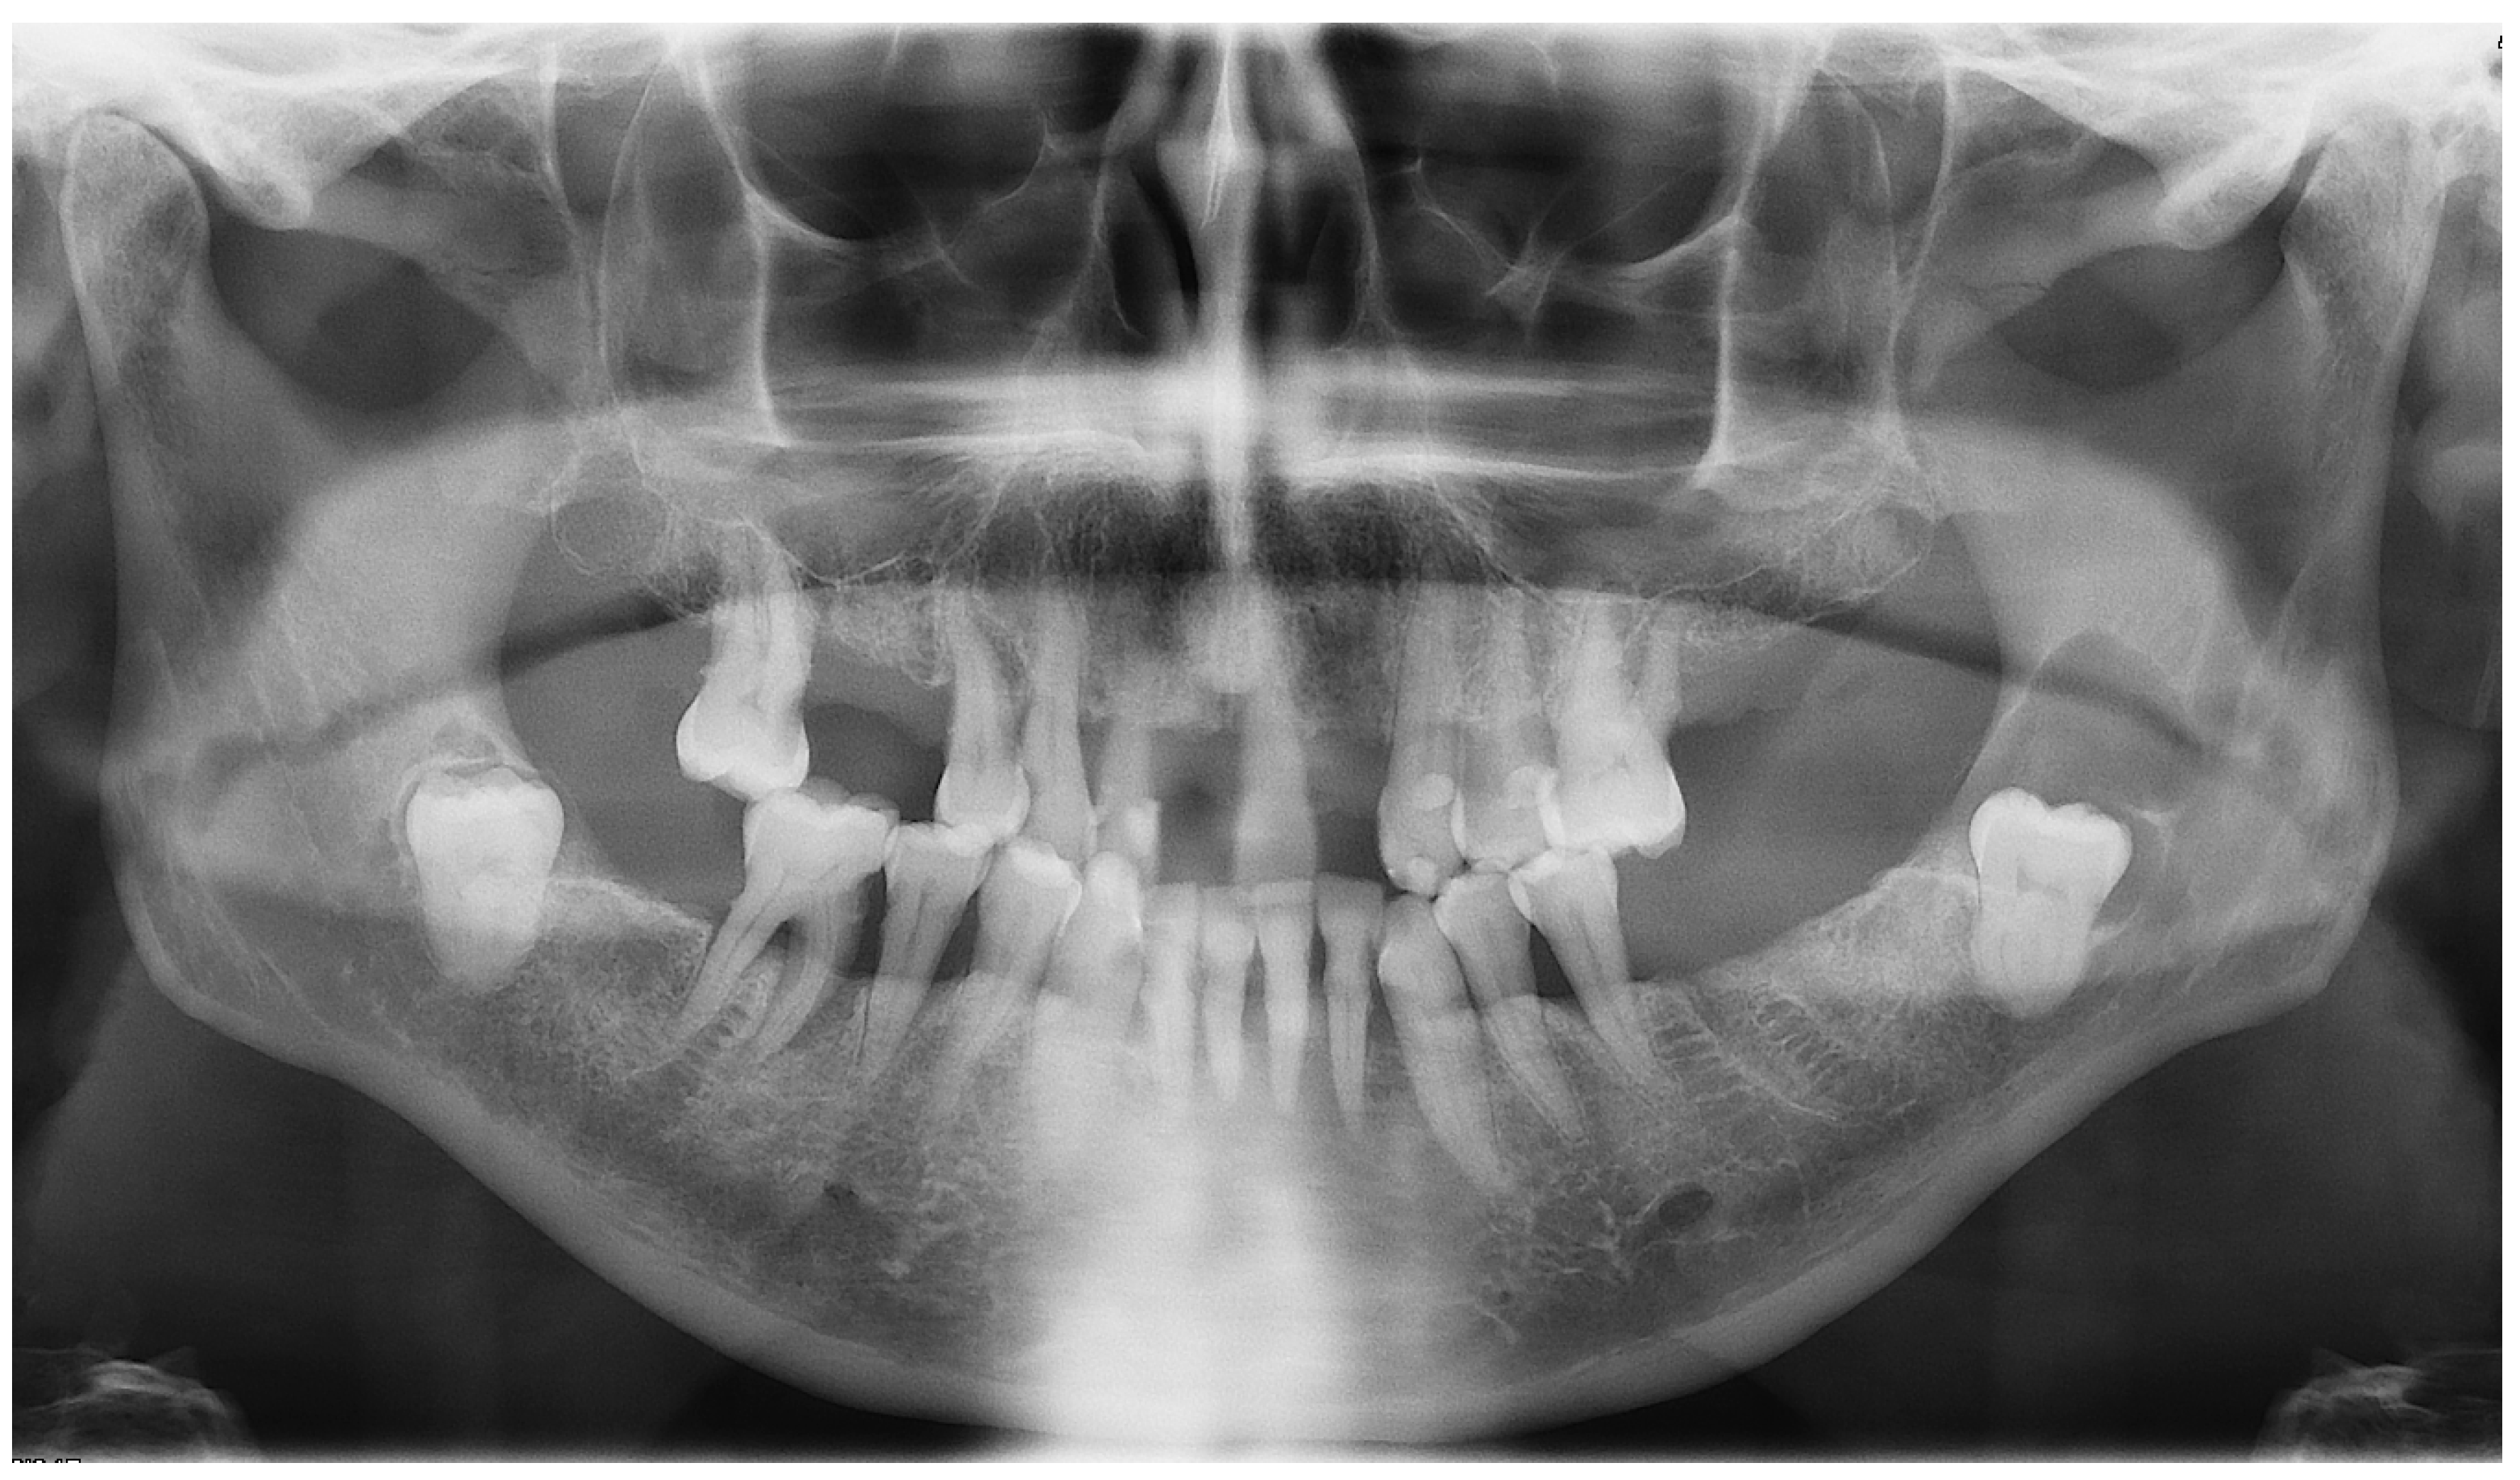

On an OPG X-ray, teeth #38 and 48 were impacted and distally orientated (Figure 10). Tooth #38 showed a radiotransparent lesion measuring 20 × 15 mm, with a well-defined border, multilocular appearance, and a thin septum, most compatible with a DC versus ameloblastoma versus odontogenic keratocyst.

Figure 10.

OPG X-ray of case #4.

On CBCT X-ray, the distal root of the impacted tooth #38 was in contact with the upper wall of the left IAC, generating a discreet deformation of the canal (Figure 11). The cyst showing a multilocular aspect was located adjacent to the crown of tooth #38 and seemed to be attached to the tooth neck. The lesion extending slightly to the ascending branch of the mandible measured 17 mm in height, 21 mm in length and 10 mm in width. In its caudal part, the lesion was in contact with the upper wall of the IAC over about 13 mm. The wall was thinned but with little impact on its internal diameter. The vestibular and lingual cortex were also strongly thinned focally. There was no periosteal reaction or fracture at the mandibular angle. On the bases of these radiological findings, the differential diagnosis included DC, ameloblastoma, and odontogenic keratocyst.